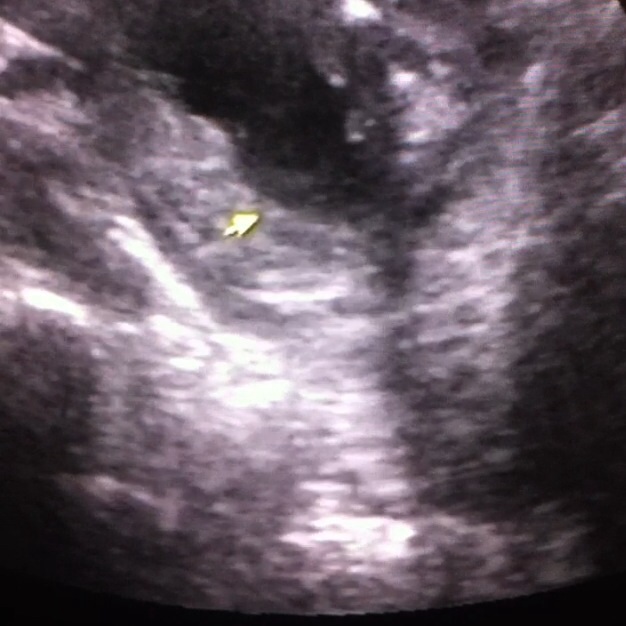

Maybe a boy

Maybe boy or swollen labia? Not sure

1st 2 pics were from 16 weeks scan everyone was unsure of those. ***NEW 3 pictures from 17 weeks scan